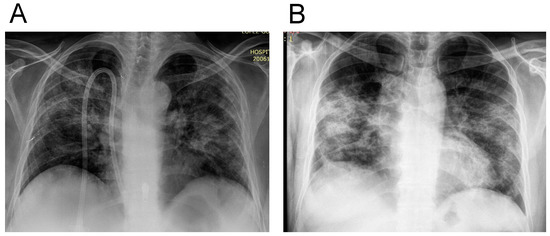

| Bilateral pneumonia n (%) | 35 (94.5) | 65 (92.8) | 0.72 |